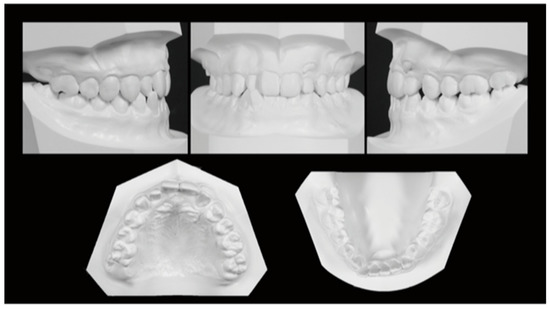

Figure 2. Initial dental casts (age, 14 years 4 months).

The facial features were symmetrical in the frontal view, with the maxillary midline coinciding with the facial midline and the mandibular midline deviated 1.5 mm to the right when smiling. The lateral view showed a straight profile. The occlusal relationship of the first molars was Angle Class I on the right side and Angle Class II on the left side, with overjet of +2.0 mm and overbite of +3.0 mm. The maxillary left canine was displaced to the labial side of the maxillary left lateral incisor, with its apex slightly and ectopically erupted. It was unclear whether the maxillary left deciduous tooth was lost prematurely during the deciduous-to-permanent dentition phase, as neither the patient nor his guardians could remember. Due to the mesial positioning of the maxillary left first molar, there was a lack of eruption space for the maxillary left canine, with an arch length discrepancy of −7.5 mm. The mandibular anterior teeth were slightly crowded, with an arch length discrepancy of −3.0 mm. The maxillary right lateral incisor and mandibular right lateral incisor were in crossbite (Figure 1 and Figure 2).